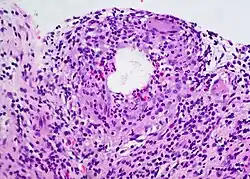

A chalazion (/kəˈleɪziən/; plural chalazia or chalazions) or meibomian cyst[4] is not a cyst but a granuloma[5] in the eyelid that results from a blocked meibomian gland.[6][7] It typically occurs in the middle of the eyelid, red, and not painful.[2] They tend to come on gradually over a few weeks.[2]

A chalazion may occur following a stye or from hardened oils blocking the gland.[2] The blocked gland is usually the meibomian gland, but can also be the gland of Zeis.[8]